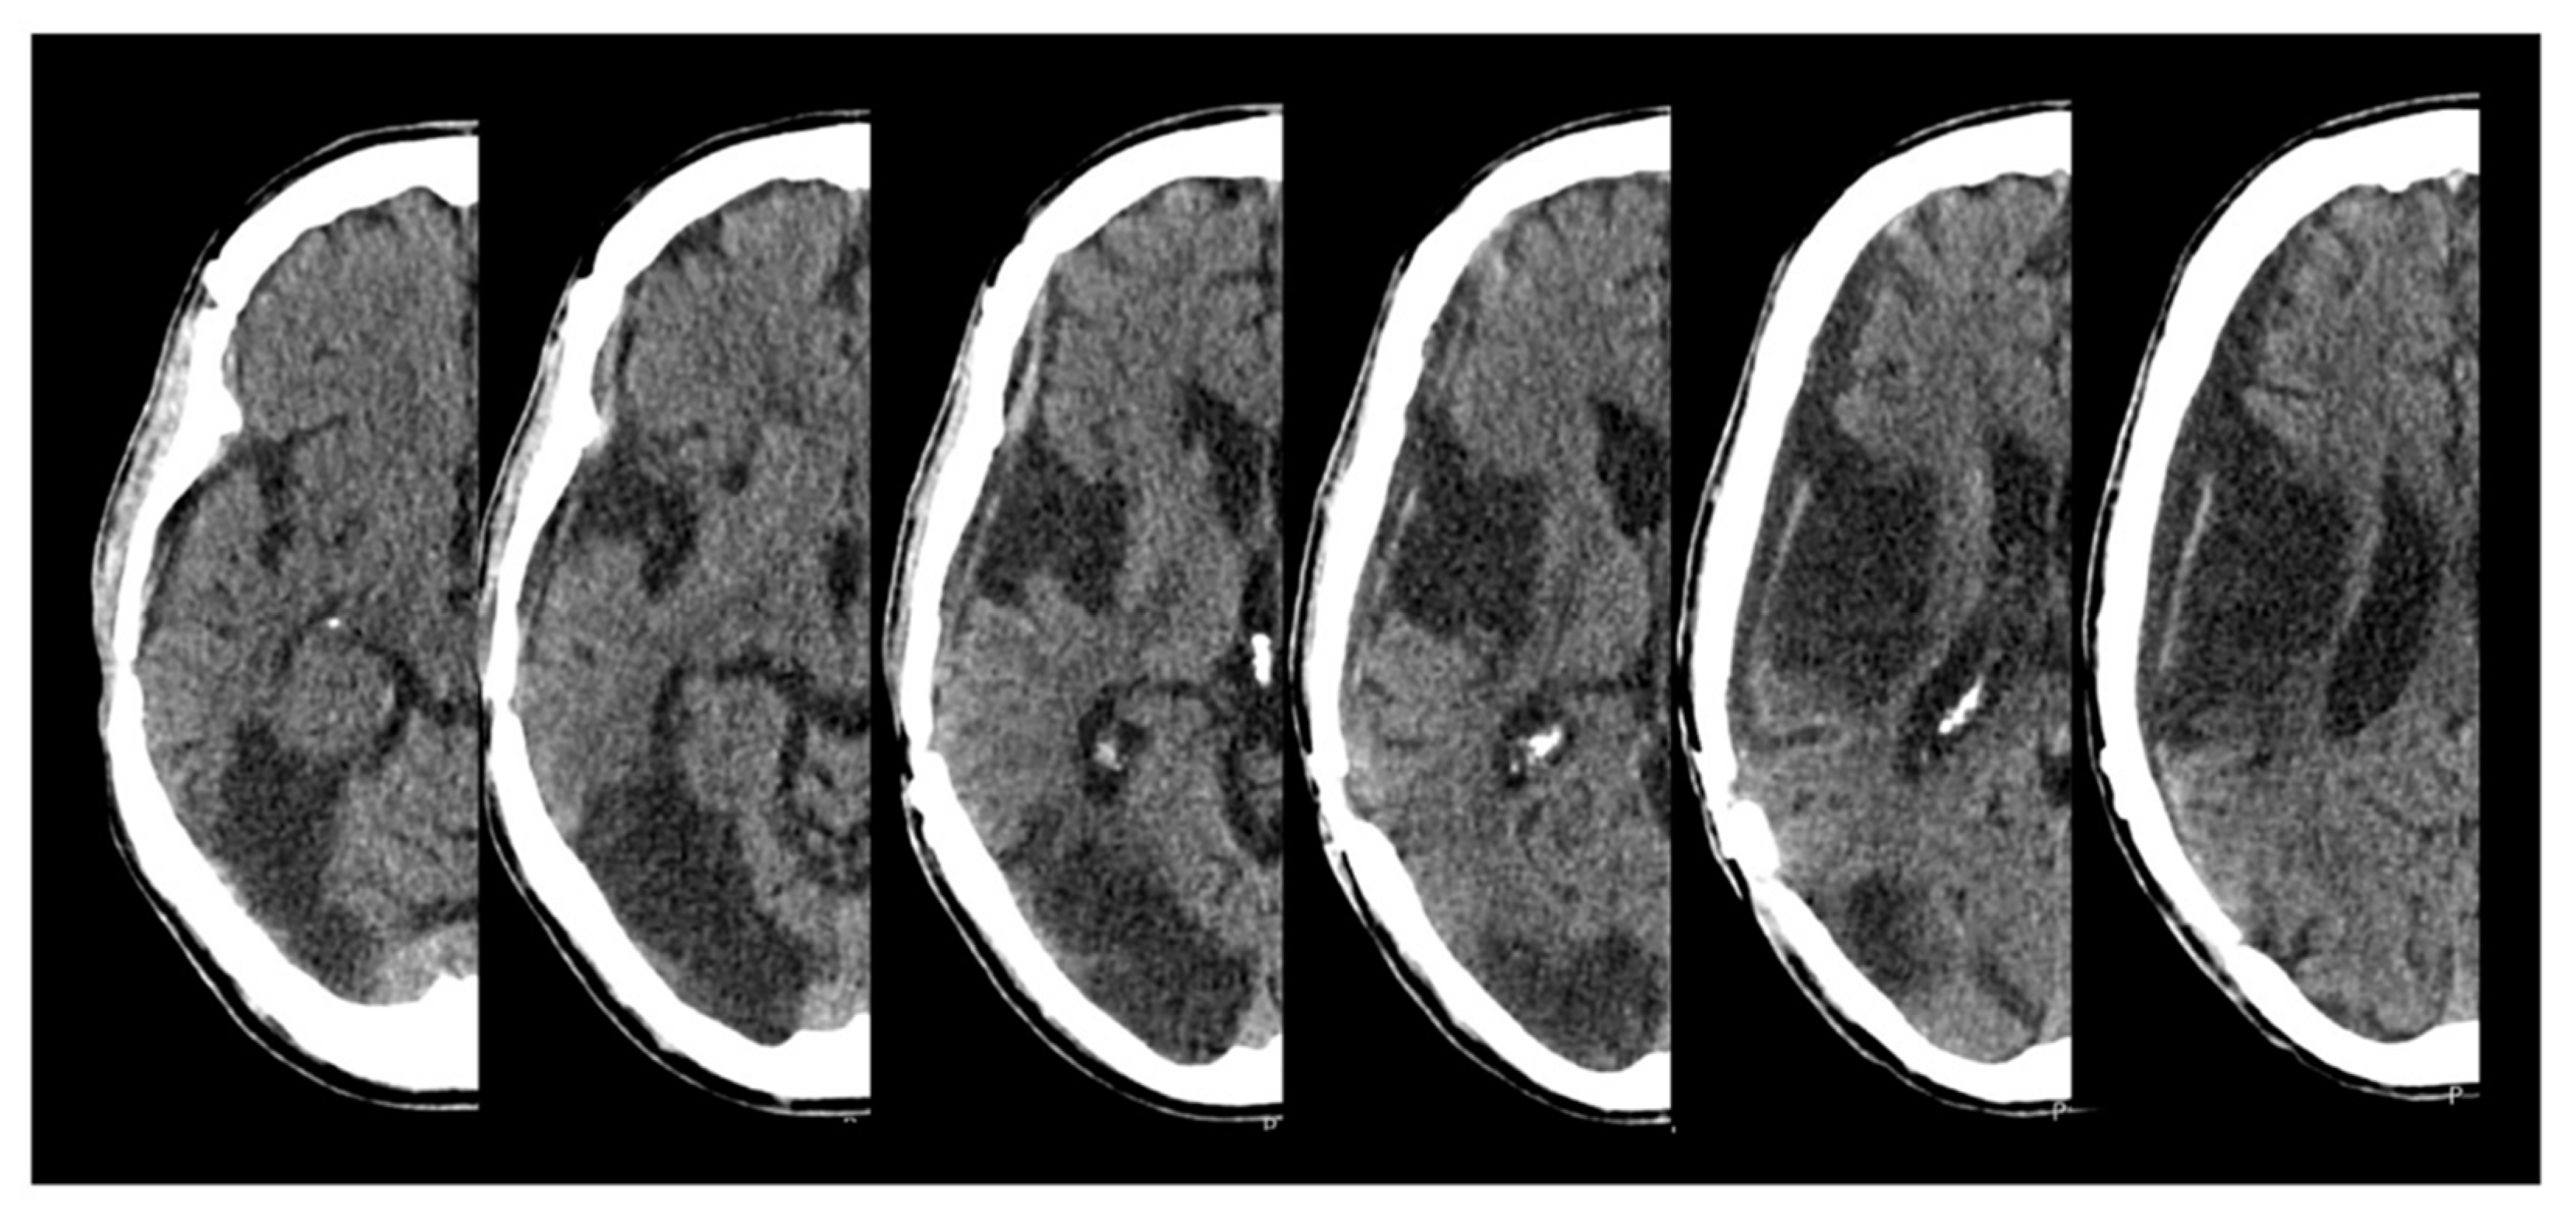

M. is a 54-year-old, right-handed man who suffered from an acute stroke in the posterior territory of the right middle cerebral artery and of the right posterior cerebral artery. The initial NIHSS score was 17. The patient presented with an arteriosclerotic occlusion of the right internal carotid artery, which was treated by an endovascular intervention and stenting. A few hours after the intervention, a lesion swelling and an expansion occurred, necessitating an emergency decompressive hemicraniectomy. The subacute CT scan presented in the figure (

Figure 1) shows an ischemic demarcation and a small subarachnoid bleeding over the right temporal lobe.